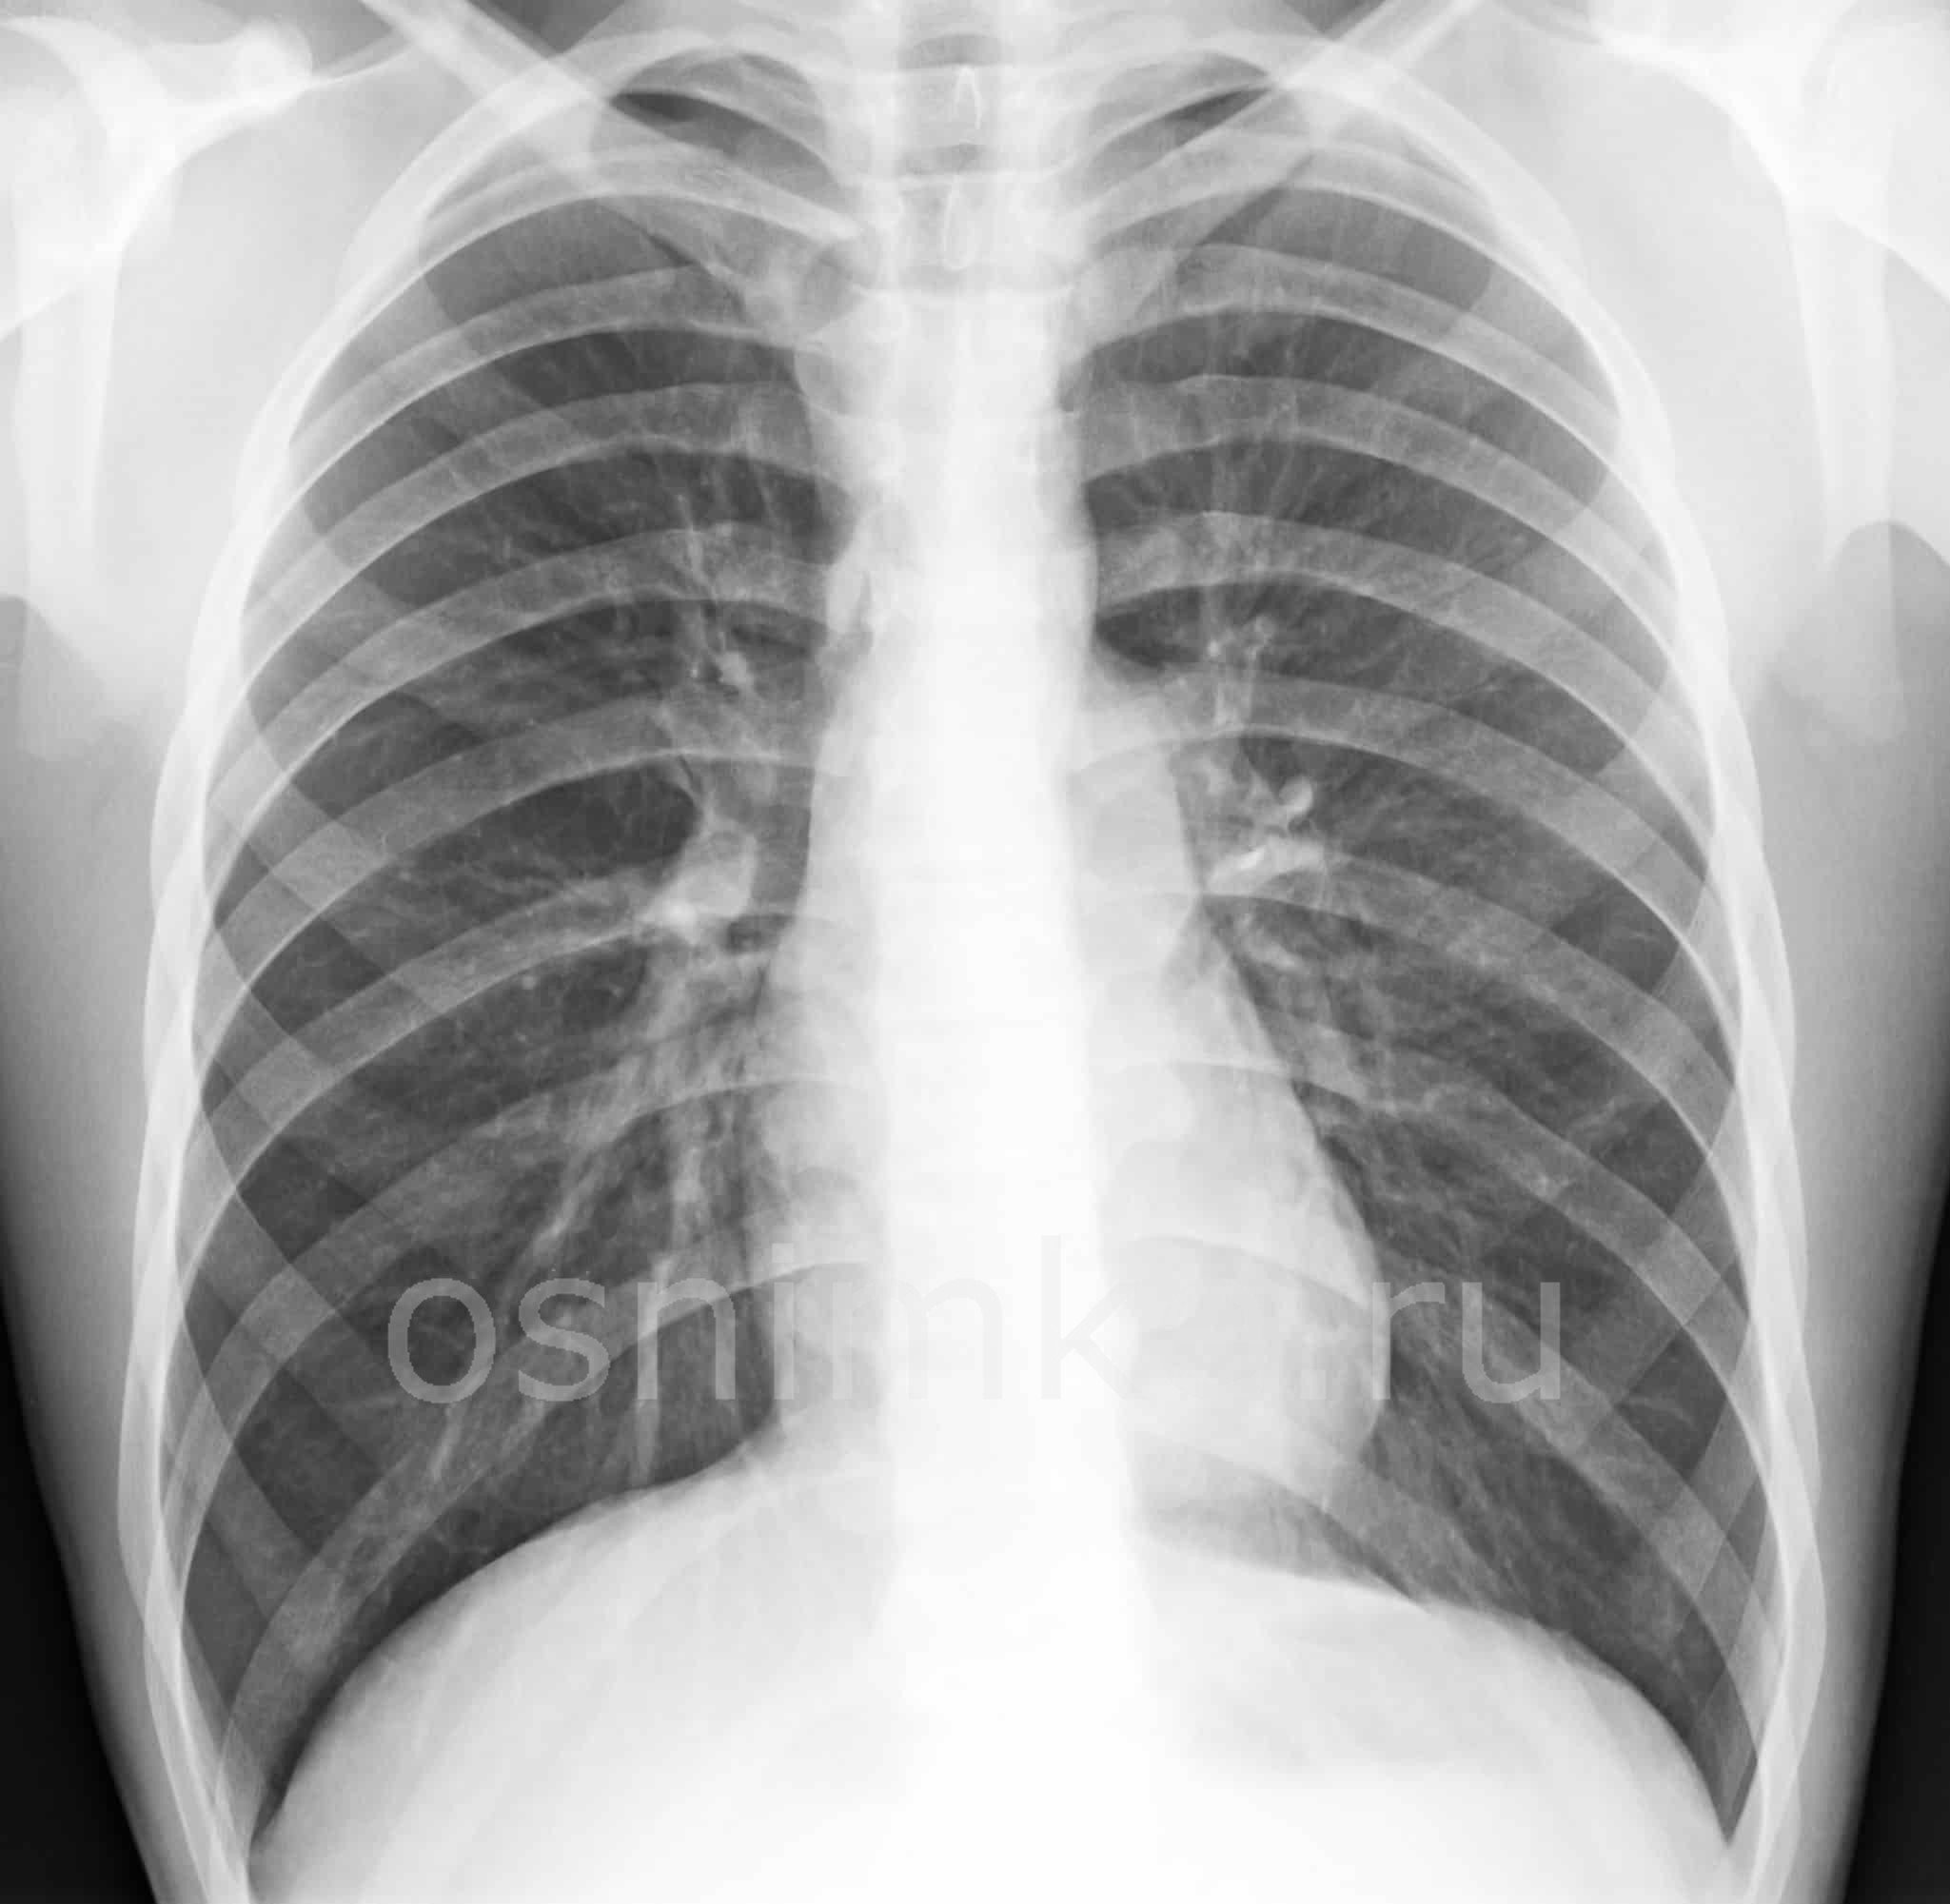

Современная диагностика включает комплекс лабораторных и инструментальных методов. Одним из них является рентгенологическое обследование. Исследование выявляет заболевание на ранних стадиях, и помогает назначить правильную терапию.

Если пациент жалуется на кашель, одышку, вялость, апатию, то назначают уже не флюорографию, а сразу рентген легких.

С помощью такого метода выявляют изменения в органах грудной клетки:

- наличие инородного тела;

- скопление воздуха или образование жидкости в бронхах, лёгких, сосудах;

- развитие инфильтратов, фиброзов, абсцессов, опухолей.